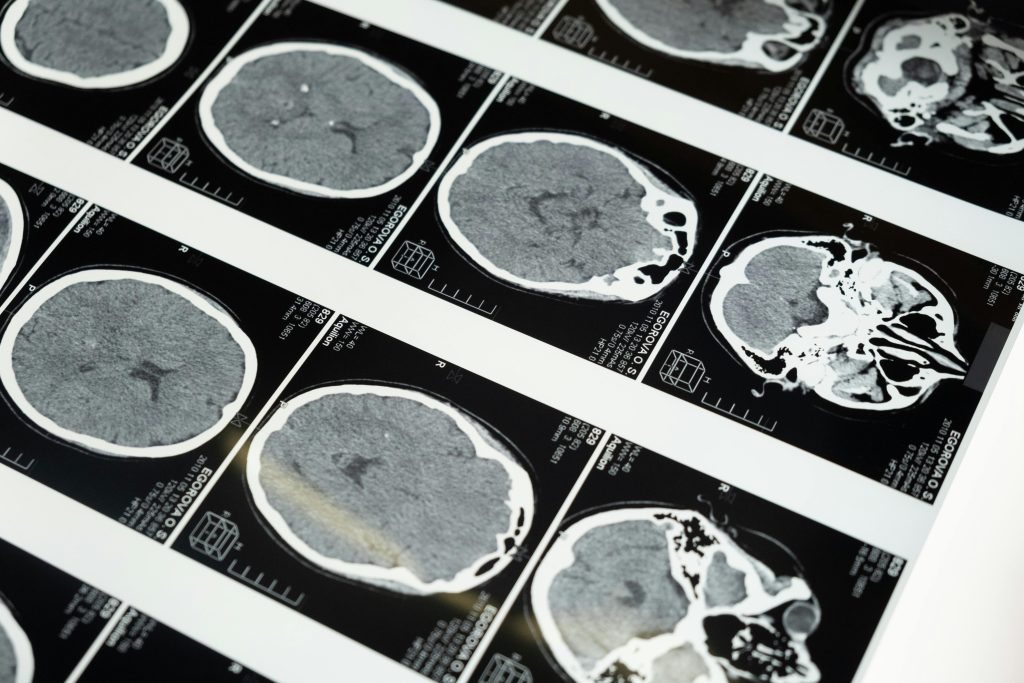

¿Debo llevar radiografías o resonancias magnéticas para la sesión?

Sí, si las tienes. Nos ayudan a entender mejor tu historial y adaptar el tratamiento a tu situación.